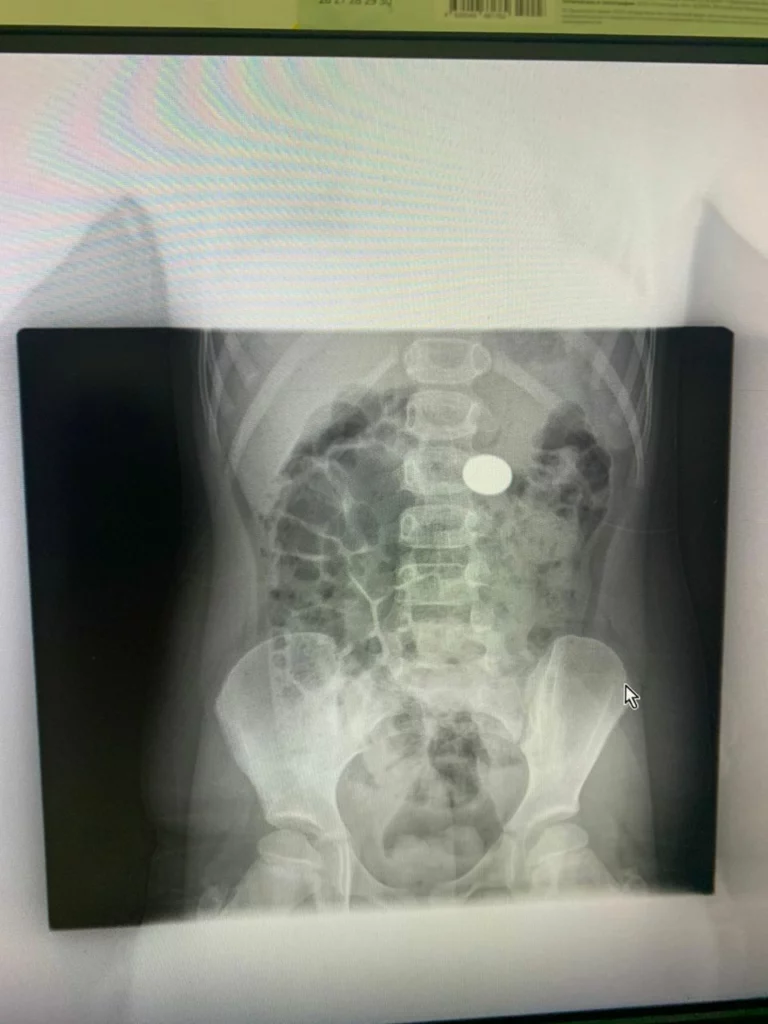

В Туапсе врачи извлекли из желудка шестилетней девочки рублевую монету

Обошлись без скальпеля. Процедуру провели в отделении эндоскопии Туапсинской районной больницы N1.

"Инородный предмет был зафиксирован рентгеном, - рассказал заведующий отделением эндоскопии ТРБ1 Гор Саакян, который и провел процедуру.

- Двое суток проводили ряд необходимых подготовительных мероприятий, а потом при помощи эндоскопа вытащили монету. Сейчас девочка чувствует себя хорошо.